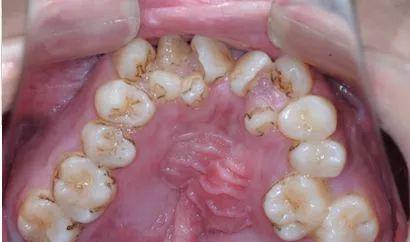

▍ 异常5:牙列拥挤

孩子牙齿不齐,要等换牙后再矫治吗?#雅悦齿科#

预计换牙后严重拥挤的病例,在替牙期提前干预有很多优点,包括减少二期治疗难度、缩短治疗时间及提高治疗效果,这对需要上学的小朋友来说有效的节约了时间成本。

*序列拔牙需慎重,需正畸专科医生评估所有检查结果后才可考虑